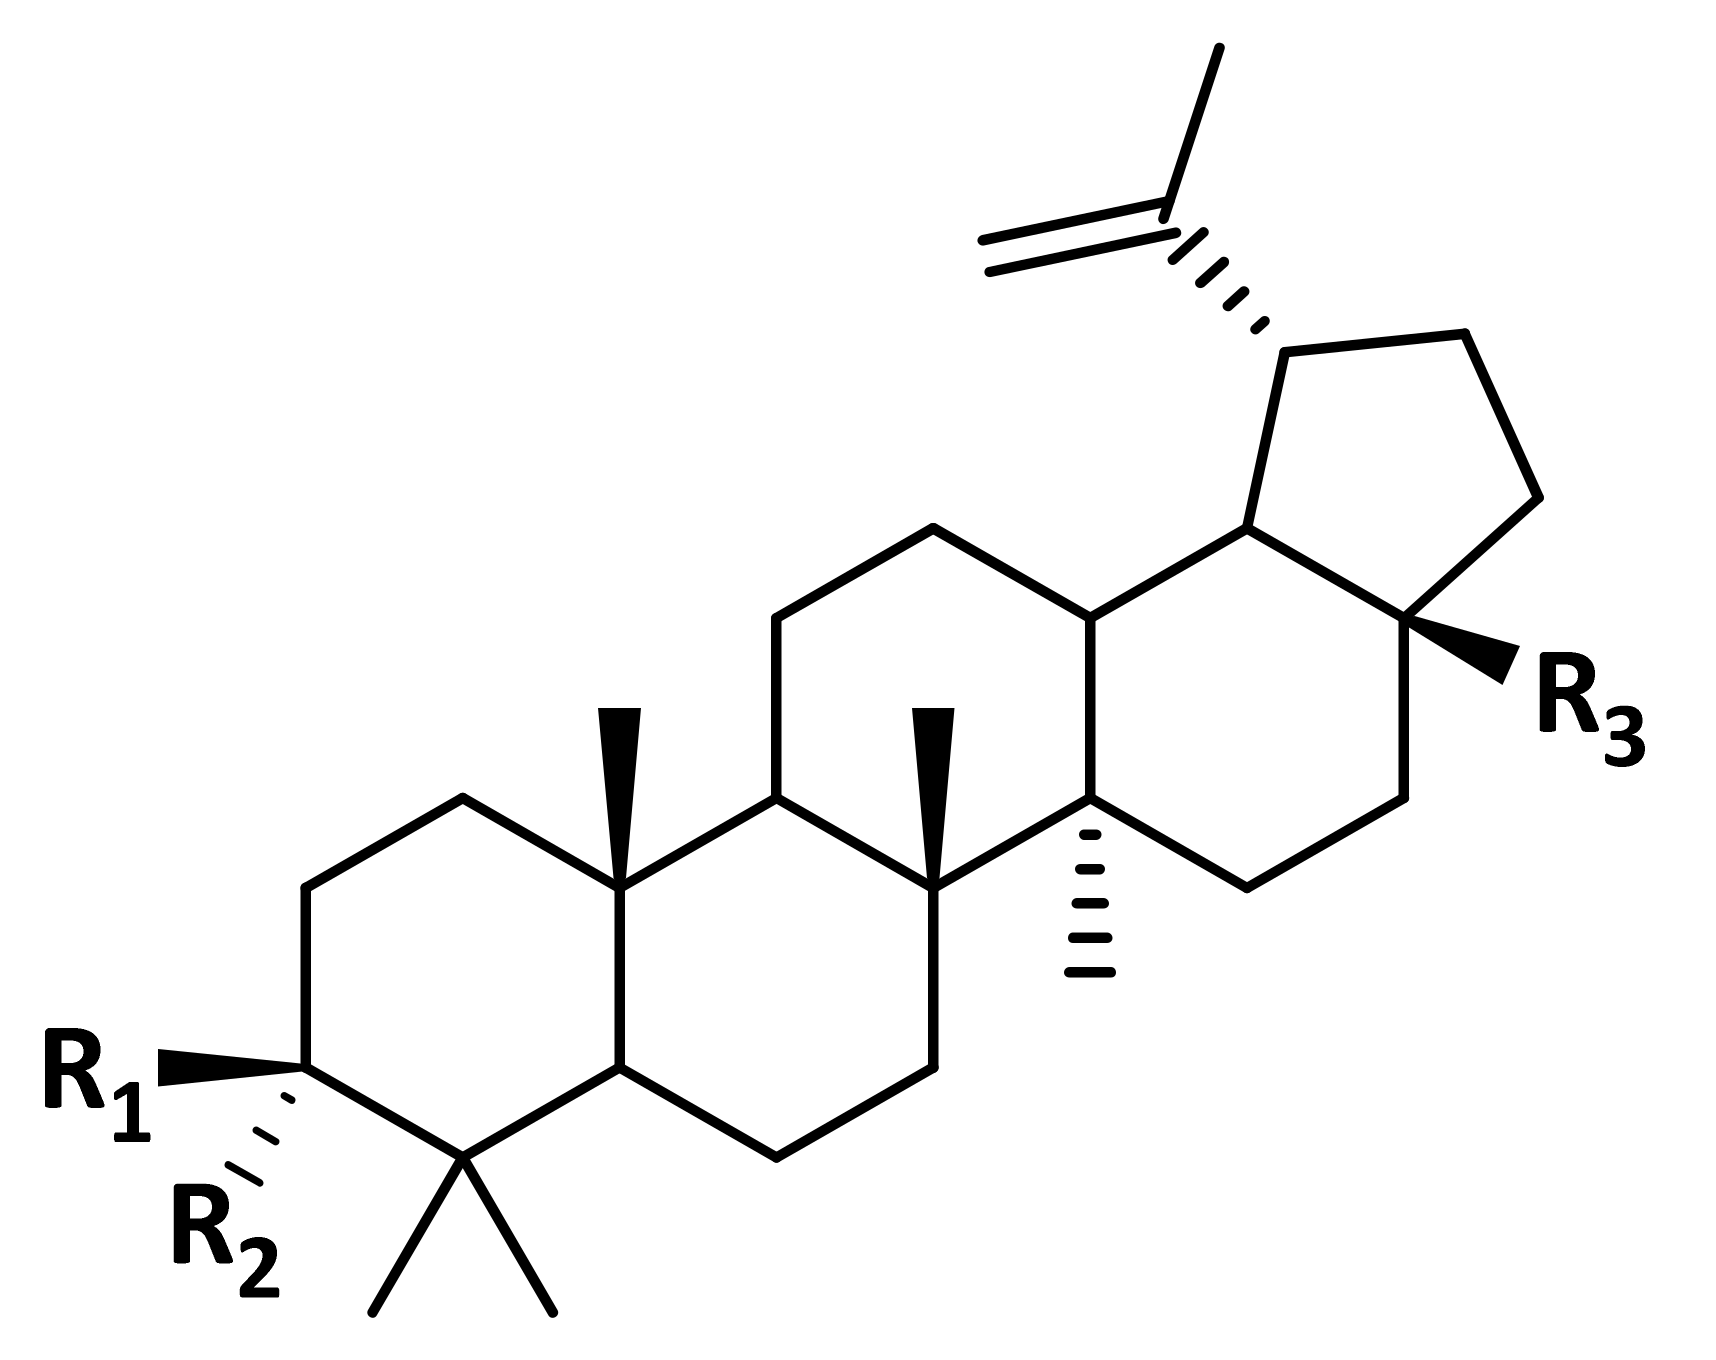

2.1. Pharmacophore Models and Molecular Docking

- Barthel, A.; Stark, S.; Csuk, R. Oxidative transformations of betulinol. Tetrahedron 2008, 64, 9225–9229. [Google Scholar]

- Flekhter, O.B.; Karachurina, L.T.; Poroĭkov, V.V.; Nigmatullina, L.P.; Baltina, L.A.; Zarudiĭ, F.S.; Davydova, V.A.; Spirikhin, L.V.; Baĭkova, I.P.; Galin, F.Z.; et al. Synthesis of the lupane group triterpenoids and there hepatoprotective activity. Russ. J. Bioorg. Chem. 2000, 26, 192–200. [Google Scholar]

- Flekhter, O.B.; Boreko, E.I.; Nigmatullina, L.R.; Pavlova, N.I.; Nikolaeva, S.N.; Savinova, O.V.; Eremin, V.F.; Baltina, L.A.; Galin, F.Z.; Tolstikov, G.A. Synthesis and antiviral activity of hydrazides and substituted benzalhydrazides of betulinic acid and its derivatives. Russ. J. Bioorg. Chem. 2003, 29, 296–302. [Google Scholar] [CrossRef]